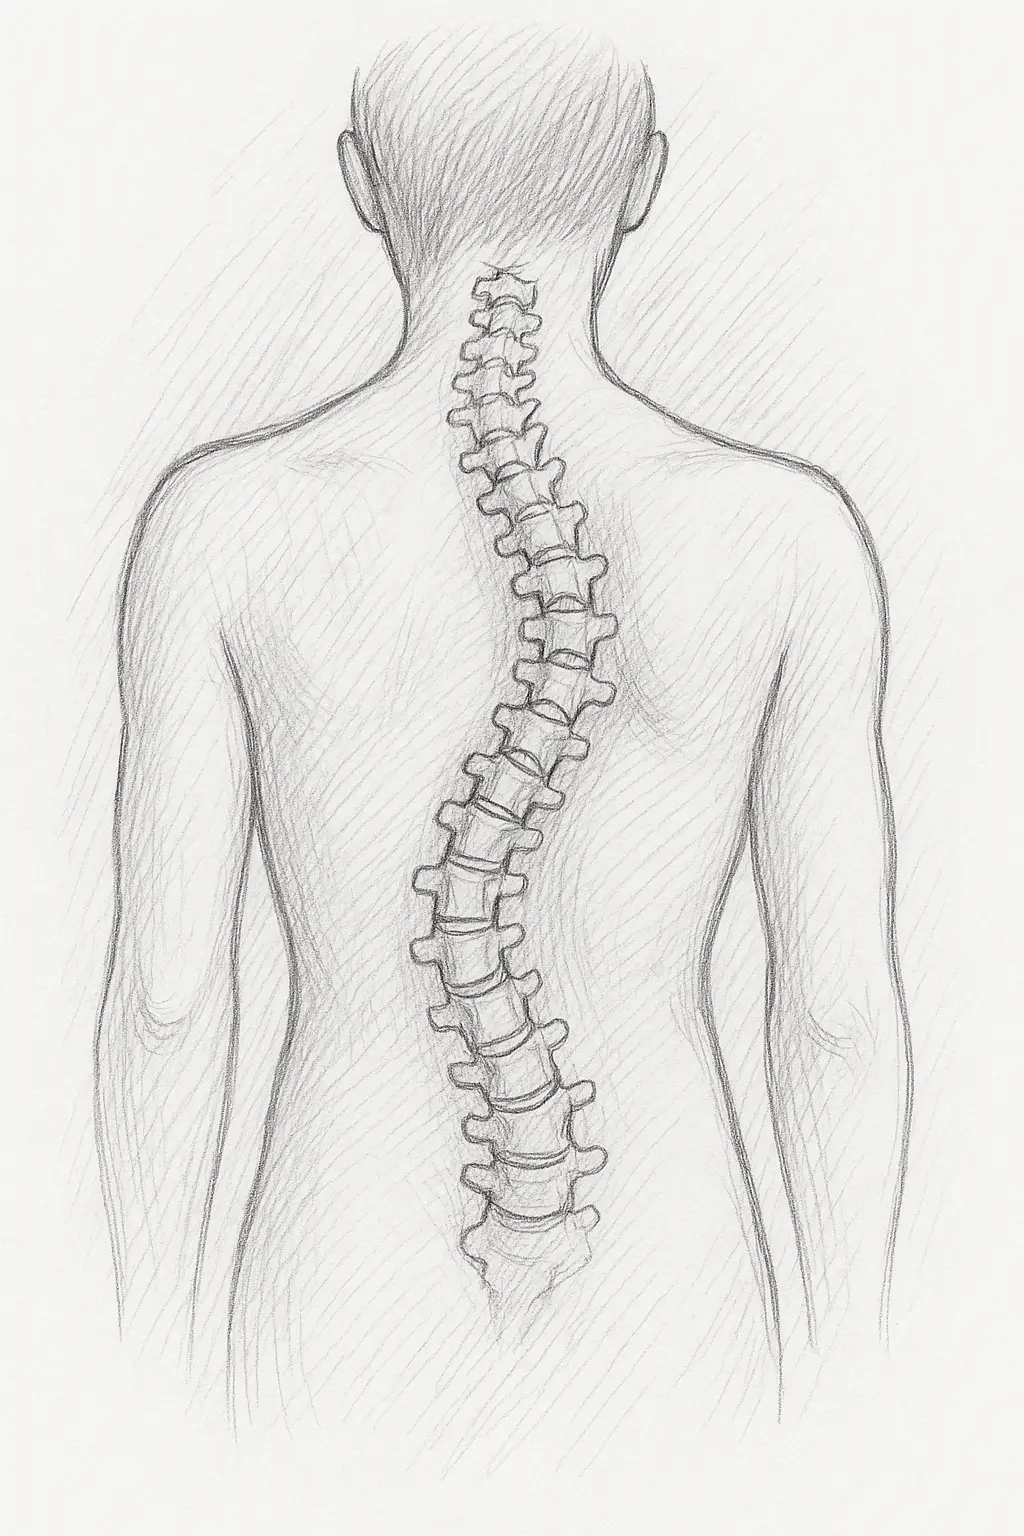

La scoliose de l’adulte : comprendre cette affection et ses implications posturales

La scoliose, souvent associée à l’enfance ou à l’adolescence, touche également les adultes.

Cette déformation tridimensionnelle de la colonne vertébrale peut provoquer des déséquilibres posturaux, des douleurs chroniques et une altération significative de la qualité de vie, allant jusqu’à limiter certaines activités quotidiennes.

La scoliose de l’adulte se distingue par une courbure anormale de la colonne vertébrale dans les trois plans de l’espace.